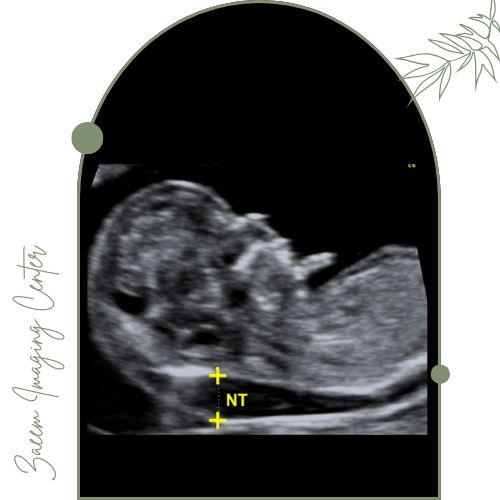

مرکز تصویربرداری پزشکی زعیم تحت مدیریت دکتر علیرضا سرزعیم (فلوشیپ مداخلهای) با همکاری دکتر سمیه زارعی و دکتر مهرناز راسته خدمات تخصصی سونوگرافی ضخامت پشت گردن جنین را براساس جدیدترین پروتکلهای غربالگری و با بهرهگیری از فناوریهای روز ارائه میکند. این تیم باتجربه با بهرهگیری از تکنولوژی پیشرفته غربالگری سلامت جنین را در بازه حساس هفتههای ۱۱ تا ۱۴ بارداری با دقت بسیار بالا و بر اساس استانداردهای بینالمللی انجام میدهد و در نهایت گزارشی دقیق، جامع و قابل فهم را در اختیار مادر و پزشک او قرار میدهد.تجهیزات پیشرفته مرکز

در این مرکز از دستگاههای پیشرفته سونوگرافی ویژه NT استفاده میشود. این تجهیزات تصویری کاملاً واضح از ضخامت شفاف پشت گردن جنین (NT) و سایر شاخصهای مهم سلامت جنین بهدست میدهند که نقش کلیدی در تشخیص سریع و دقیق اختلالات ژنتیکی دارند.اطلاعات جمعآوری شده توسط متخصصان با بالاترین استانداردها تحلیل و گزارش میشود تا مادران با اطمینان روند بارداری را طی کنند.